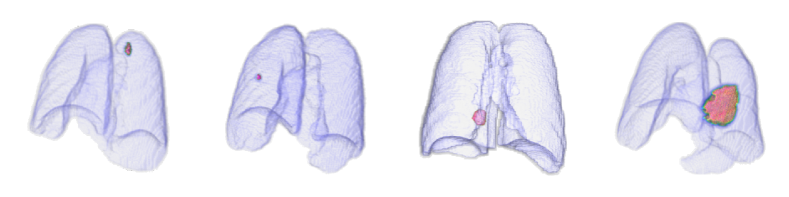

3.5 External validation using public lung cancer CT dataset

The experimental results presented thus far (Sections 3.4.1, 3.4.2, 3.4.3, and 3.4.4) show verification using SMC internal data (i.e., anomaly detection for pneumonia, tuberculosis, and both diseases). In this section, we further confirm the superiority of the proposed VMPR-UAD by demonstrating its high performance on external data, that is, the MSD dataset with 95 3D stacks showing lung cancer [35]). The anomaly detection results of VMPR-UAD are shown as ROC curves with AUC in Fig. K. VMPR-UAD provides high anomaly detection performance (at least 0.98) for different numbers of projections, with a higher diagnostic performance achieved when using more projections. As this trend is the same as that obtained from internal data, we can infer that VMPR-UAD consistently provides high diagnostic performance regardless of the CT dataset.

Finally, we evaluated the 3D abnormal (lesion) localization performance of the proposed VMPR-UAD. Of the 63 cancer cases in the MSD dataset with ground-truth annotations available, we excluded two cases (cases 38 and 96) of incorrect annotation or showing other diseases. We calculated whether the cancer area predicted by VMPR-UAD (binarized at a certain high-probability threshold) overlapped with the annotated cancer area. As a result, 57 of the 61 cases showed overlapping, demonstrating that VMPR-UAD can localize 3D lung anomalies (cancer in this case) with an accuracy of 93. Some localization examples in 3D data are shown in Fig. L. The red points in Fig. L(b) show the 3D cancer locations that the proposed method estimates with the highest confidence (i.e., location of highest pixel value in the 3D anomaly map). The red points in Fig. L(a) show the ground-truth cancer location. The ground truth and prediction shown in Fig. L confirm that VMPR-UAD correctly finds the lung anomaly 3D region. More detailed visualization results are available in the Supplementary Material. The prediction consistency can also be observed in 2D slices, as shown in Fig. M, where our anomaly localization map indicates correct cancer regions. Hence, the proposed VMPR-UAD can automatically localize or segment lesions without requiring any lesion information (i.e., using only CT slices from healthy subjects) for training.